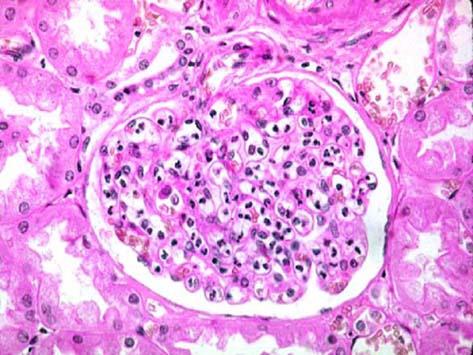

问题 患者男性,10岁,3周前咽痛,近1周出现腰区疼痛,浮肿尿少,尿蛋白(+),尿红细胞1025/HP,红细胞管型01/HP。肾穿刺活检镜下如图所示,该患者所患的疾病为 ( )

选项 A.隐匿性肾炎 B.慢性肾小球肾炎 C.急性弥漫性增生性肾小球肾炎 D.急进性肾小球肾炎 E.急性肾盂肾炎

答案 C